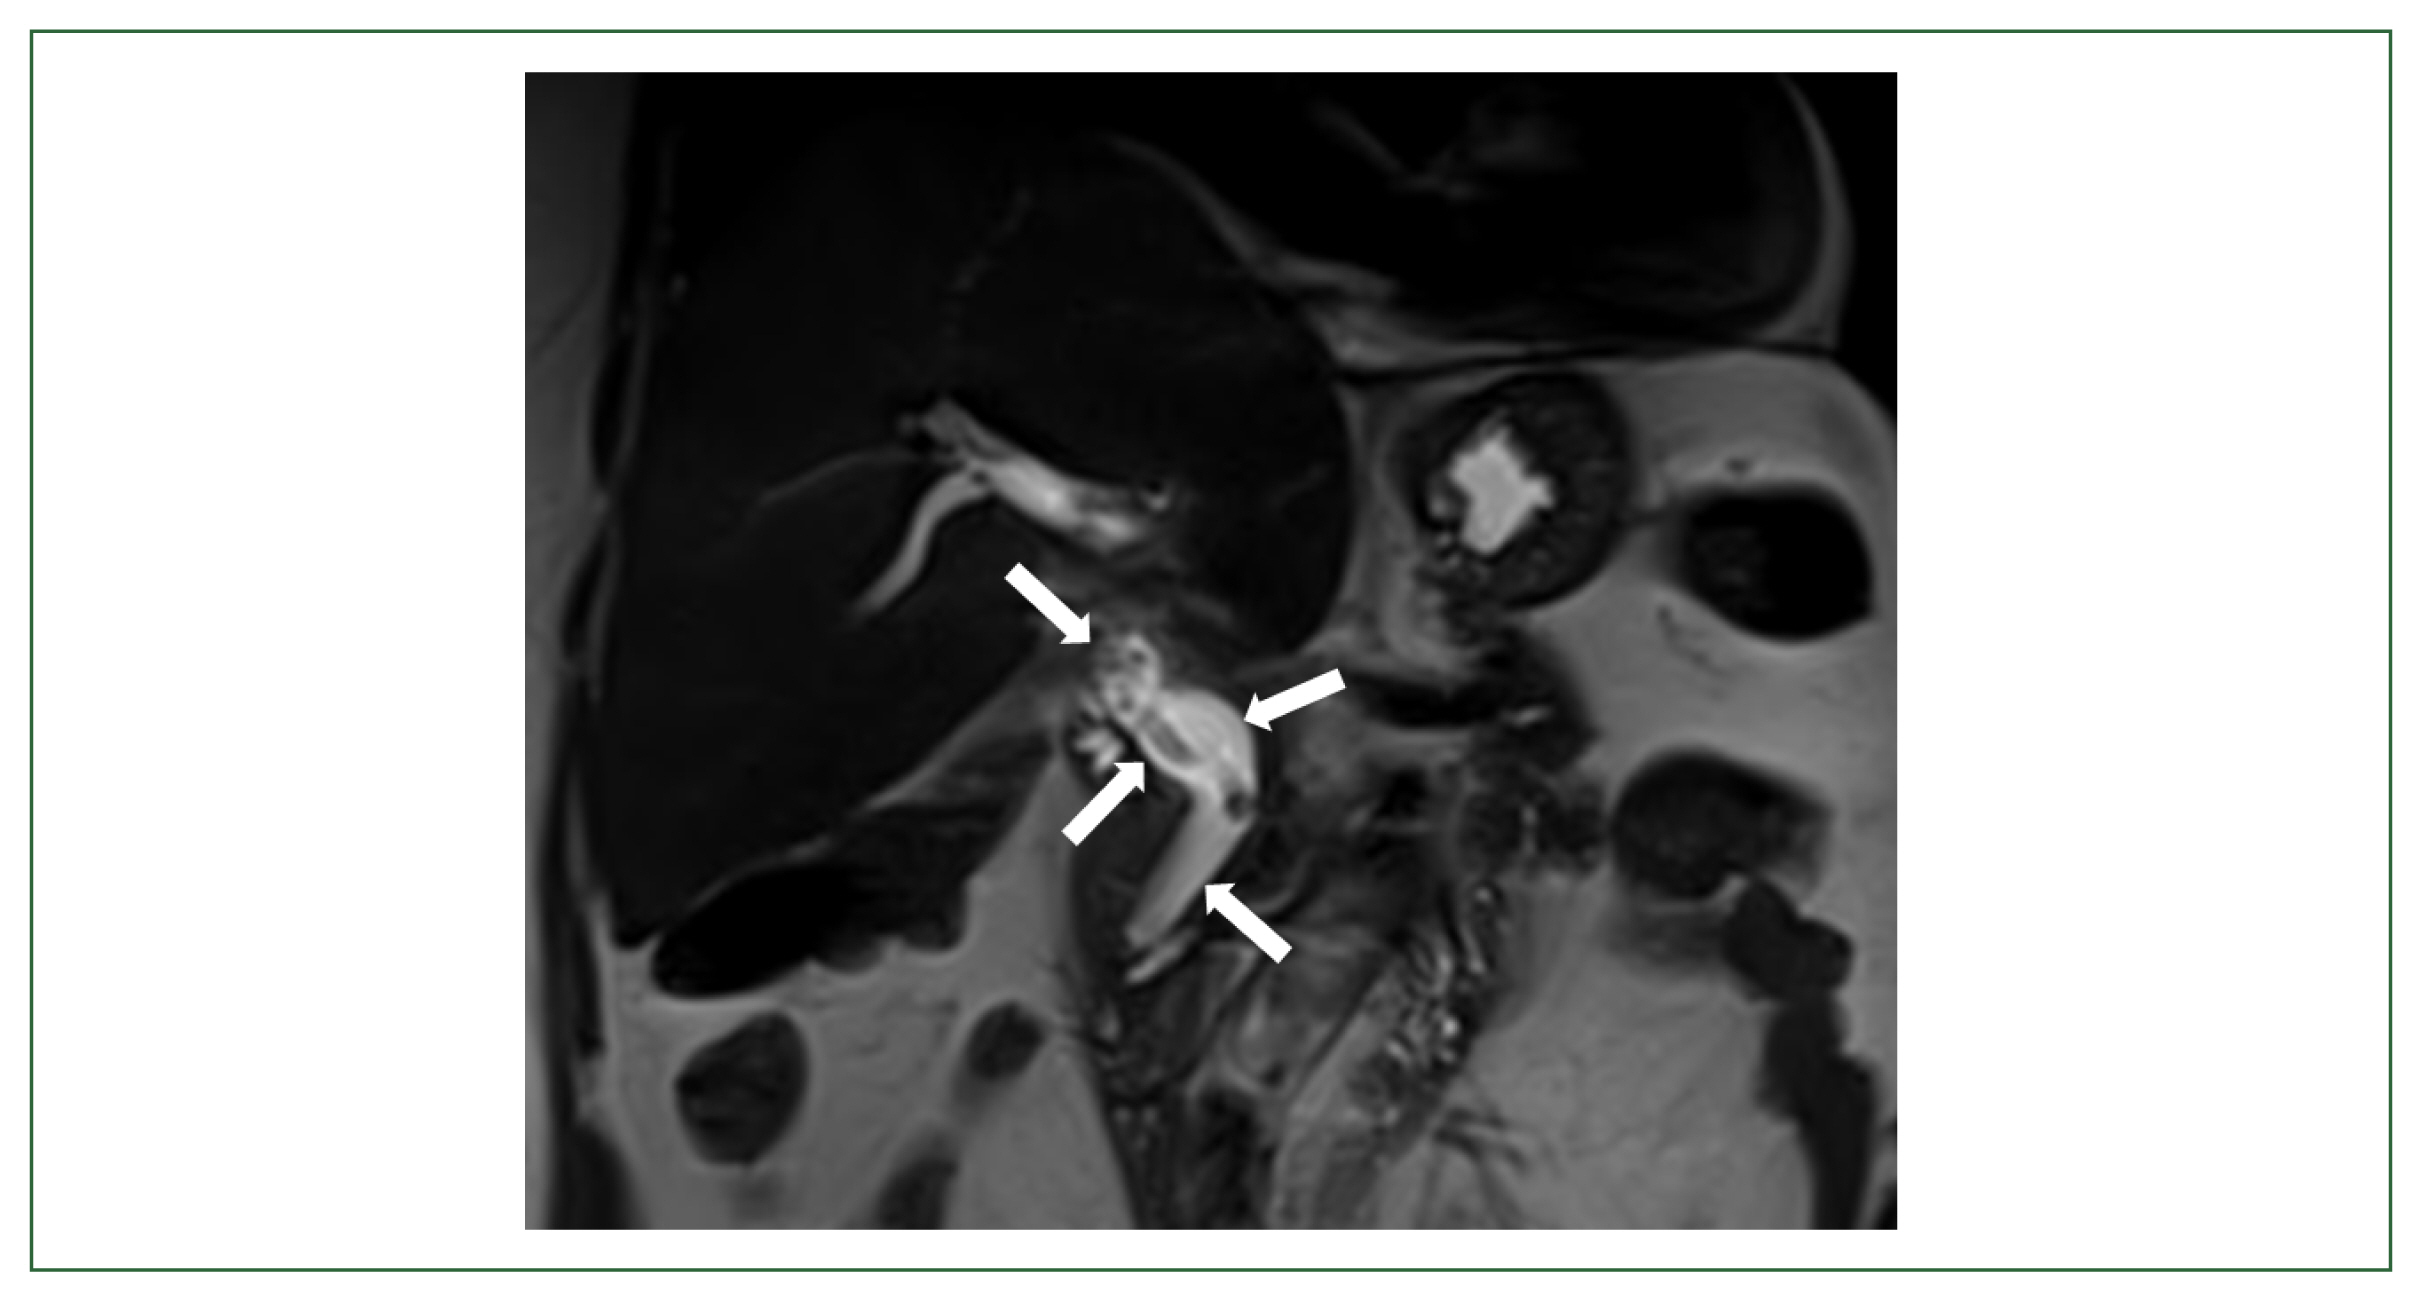

Ascaris lumbricoides causes one of the most common soil-transmitted helminthiases globally. The worms mostly infect the human small intestine and elicit negligible or nonspecific symptoms, but there are reports of extraintestinal ectopic ascariasis. We describe a rare case of biliary ascariasis mistaken for biliary stent in a 72-year-old female patient with a history of liver resection. She visited our outpatient clinic complaining of right upper quadrant pain and fever for the past week. She had previously undergone left lateral sectionectomy for recurrent biliary and intrahepatic duct stones 2 years ago. Besides mildly elevated gamma-glutamyl transferase levels, her liver function tests were normal. Magnetic resonance cholangiopancreatography revealed a linear filling defect closely resembling an internal stent from the common bile duct to the right intrahepatic bile duct. A live female A. lumbricoides adult worm was removed by endoscopic retrograde cholangiopancreatography (ERCP). Despite a significant decrease of the ascariasis prevalence in Korea, cases of biliary ascariasis are still occasionally reported. In this study, a additional case of biliary ascariasis, which was radiologically misdiagnosed as the biliary stent, was described in a hepatic resection patient by the worm recovery with ERCP in Korea.